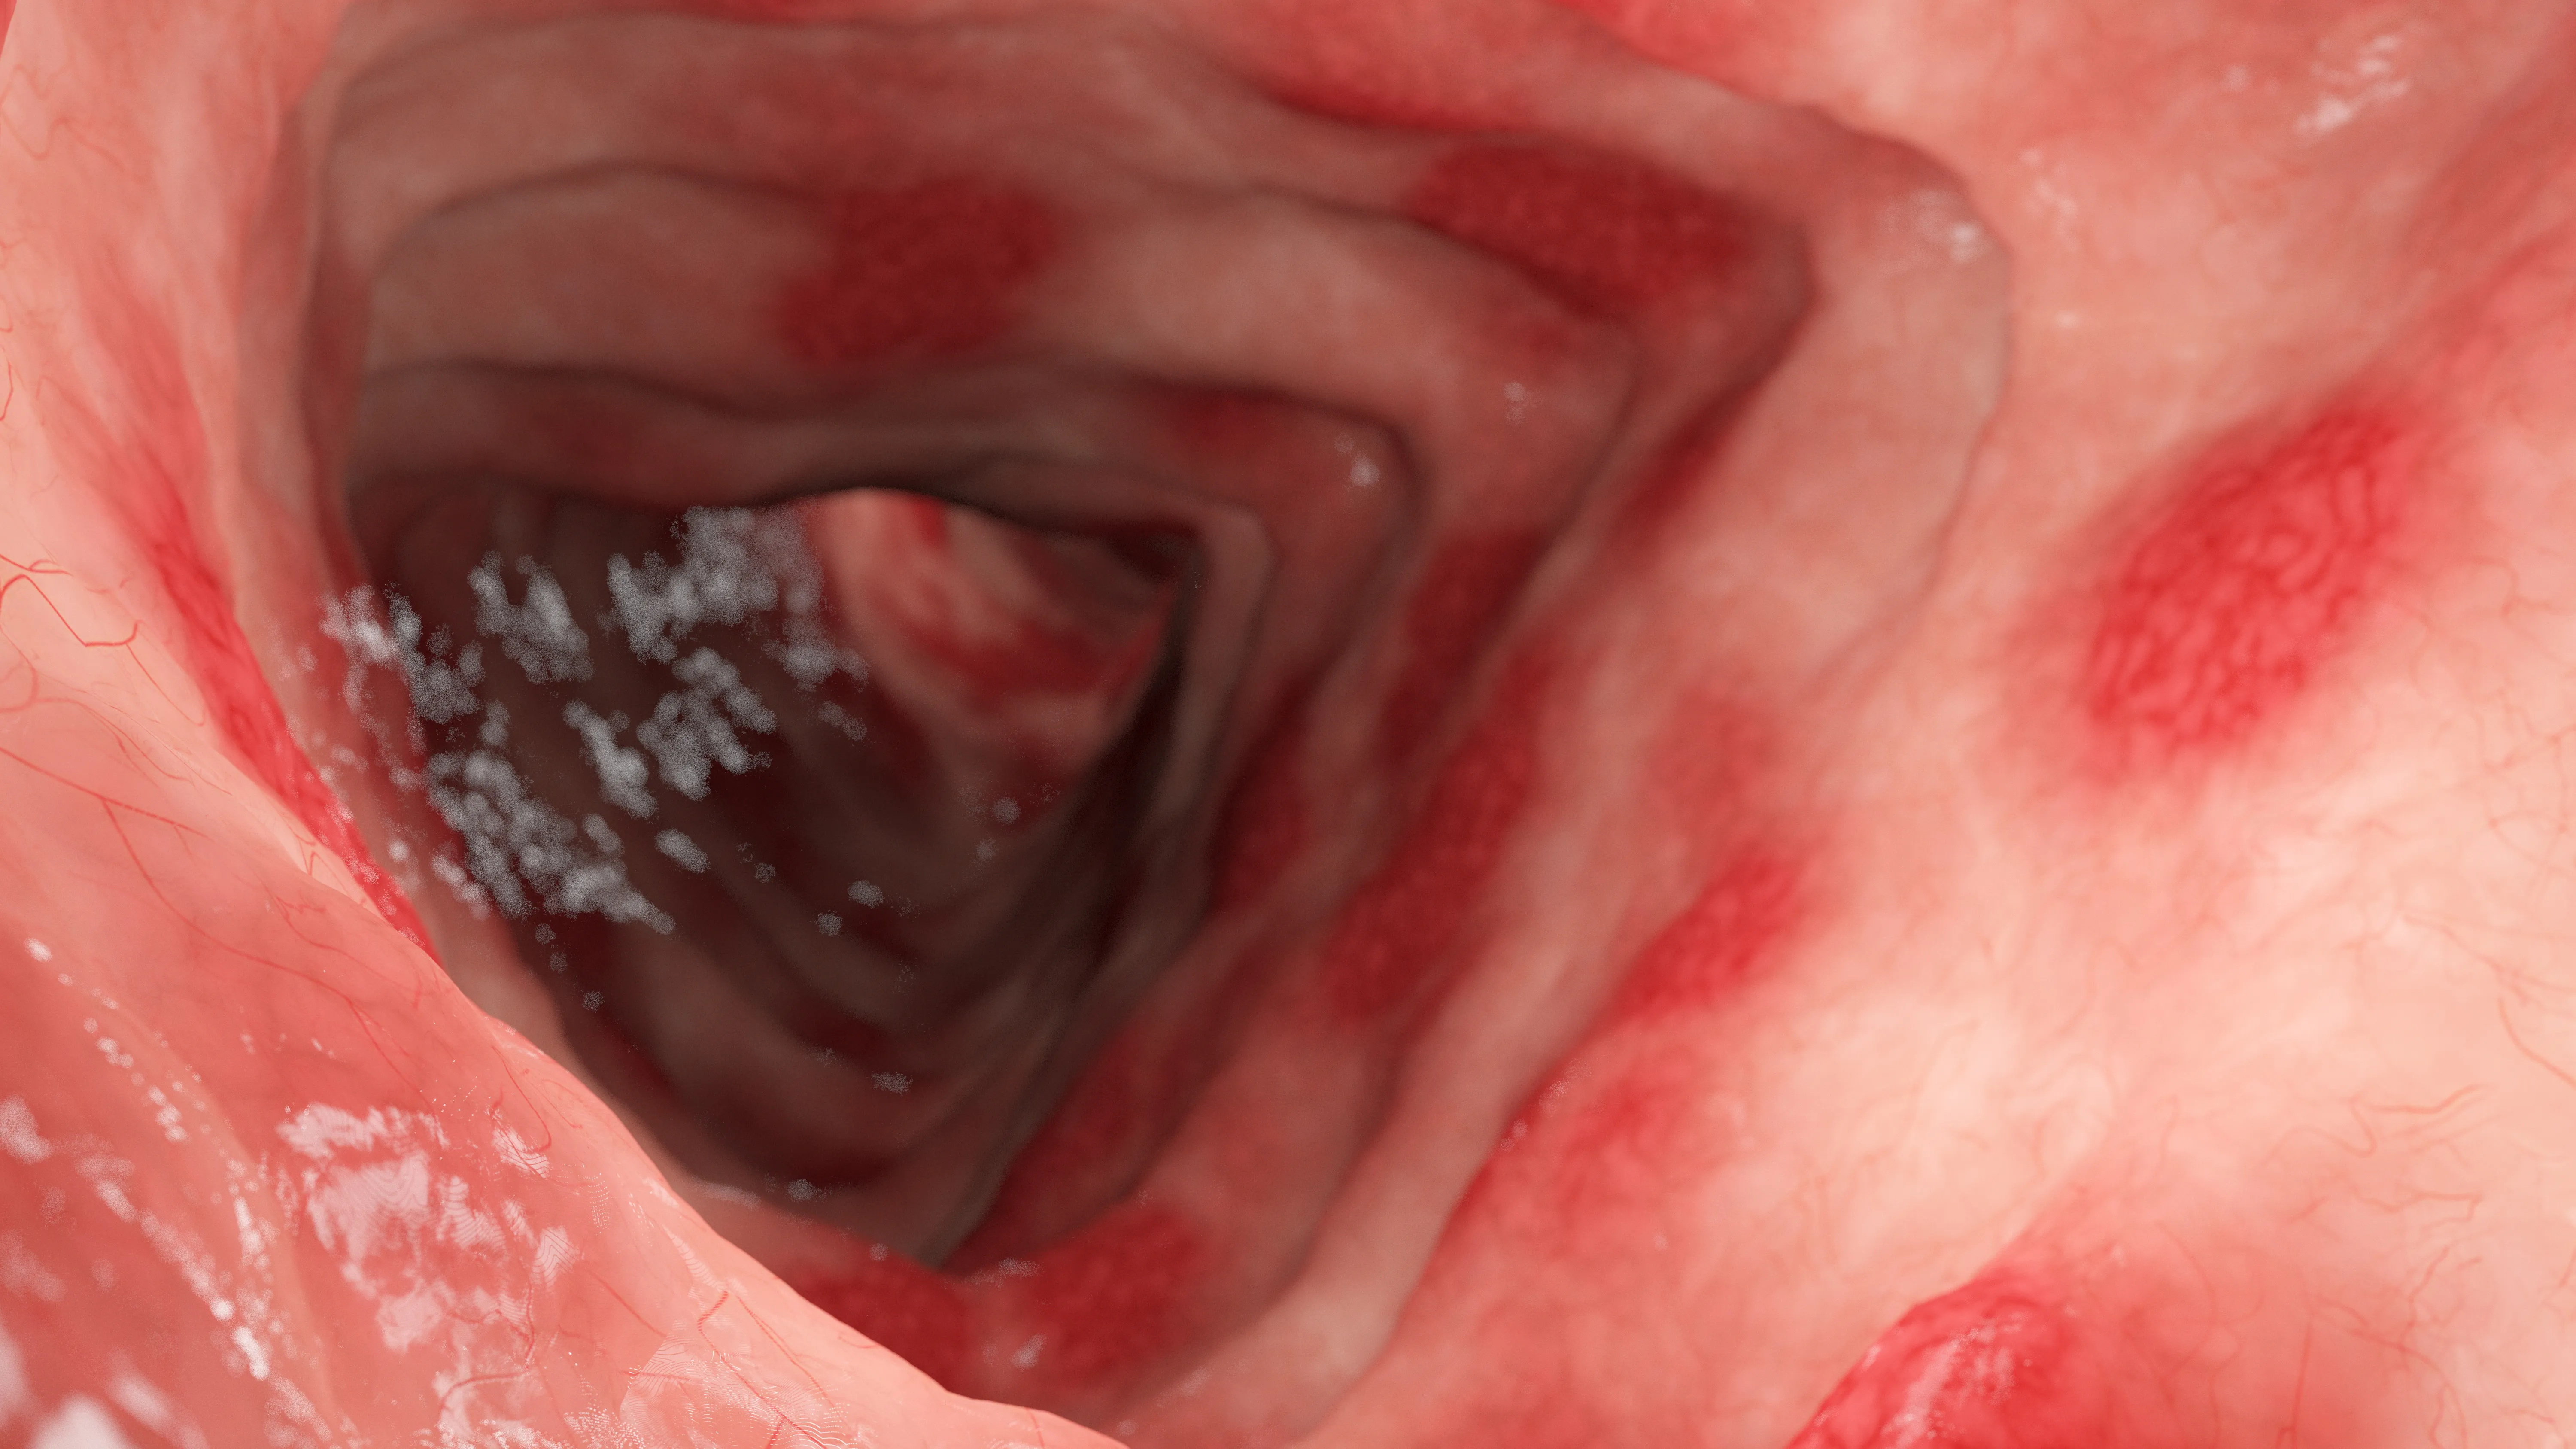

潰瘍性大腸炎

潰瘍性大腸炎(UC:Ulcerative Colitis)は、大腸の粘膜に慢性的な炎症や潰瘍が生じる病気で、炎症性腸疾患の一つです。

症状が起こる「活動期(再燃期)」と、症状が治まる「寛解期」があり、治療を中断するとぶり返してしまうことが多いため、慎重にコントロールしていくことが大切になります。

免疫反応の異常、腸内細菌、遺伝、食べ物などが複雑に影響していると考えられていますが、発症の原因は明らかになっていません。

潰瘍性大腸炎は完全に治すことが難しく、厚生労働省から難病指定を受けている病気ですが、治療を続けることで発症前の状態に近い生活を送ることが可能です。

大腸カメラ検査では、びらんや潰瘍、出血の程度を直接確認でき、病変の範囲や重症度を評価します。

また、採取した組織を病理組織検査で調べることで確定診断に活かします。

症状の程度と炎症の広がりに応じて治療内容を調整するためにも、大腸カメラは欠かせない検査です。

主な症状

- 下痢

- 血便・粘血便

- 腹痛

- 発熱